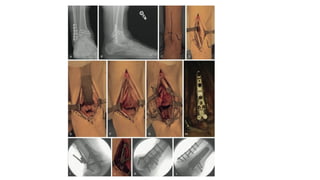

A and B, End-stage ankle arthritis. C and D, After mini-incision ankle arthrodesis;

use of “home run” screw from posterolateral tibial into talar neck/head distally

A and B,End-stage ankle arthritis. C and D, After mini-incision ankle arthrodesis; use of “home run” screw from posterolateral tibial into talar neck/head distally